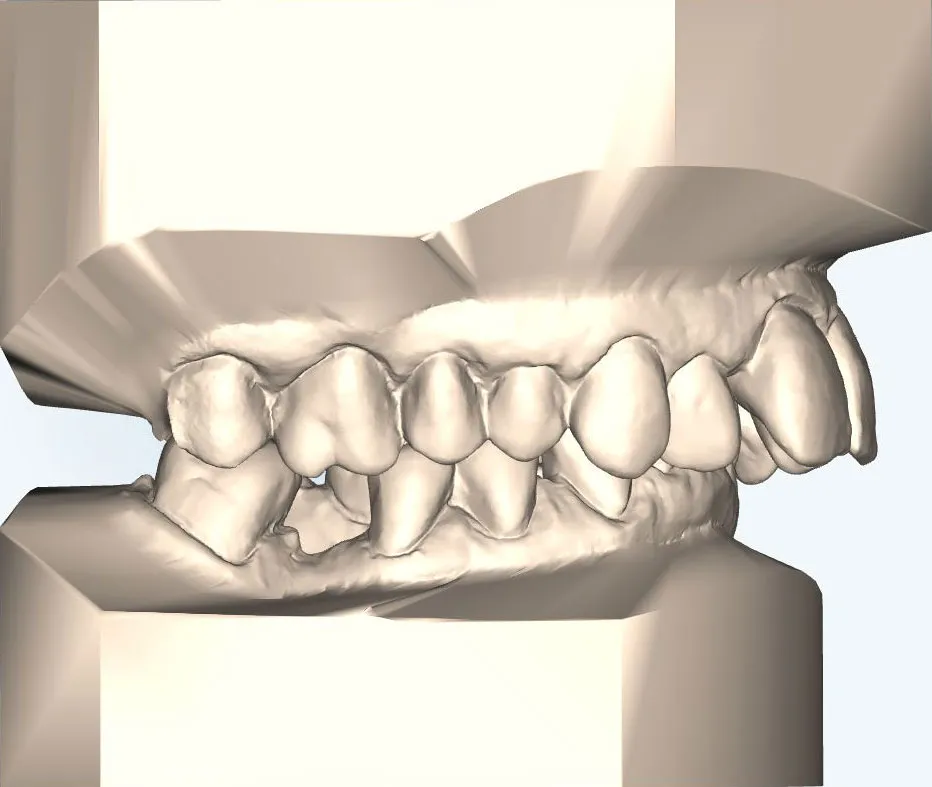

Wenn Ober- und Unterkiefer unterschiedlich stark entwickelt sind, kann nach abgeschlossenem Wachstum eine kombinierte kieferorthopädisch-kieferchirurgische Behandlung notwendig werden. Dabei wird die Position eines oder beider Kiefer chirurgisch korrigiert, um Funktion und Ästhetik nachhaltig zu verbessern.

Für die kieferorthopädische Vor- und Nachbehandlung verwenden wir festsitzende Zahnspangen, die während und nach der Operation getragen werden müssen.

Für Patienten, die eine unauffällige Lösung bevorzugen, bieten wir die linguale Zahnspange an:

- Sie wird auf der Innenseite der Zähne befestigt und ist von außen nahezu unsichtbar.

- Die lingualen Zahnspange erziehlt durch ihre Individualisierung und ihrer lingualen Position eine sehr effiziente Kraftübertragung im Vergleich zur klassischen, festen Zahnspange – dabei ist sie zudem deutlich diskreter.